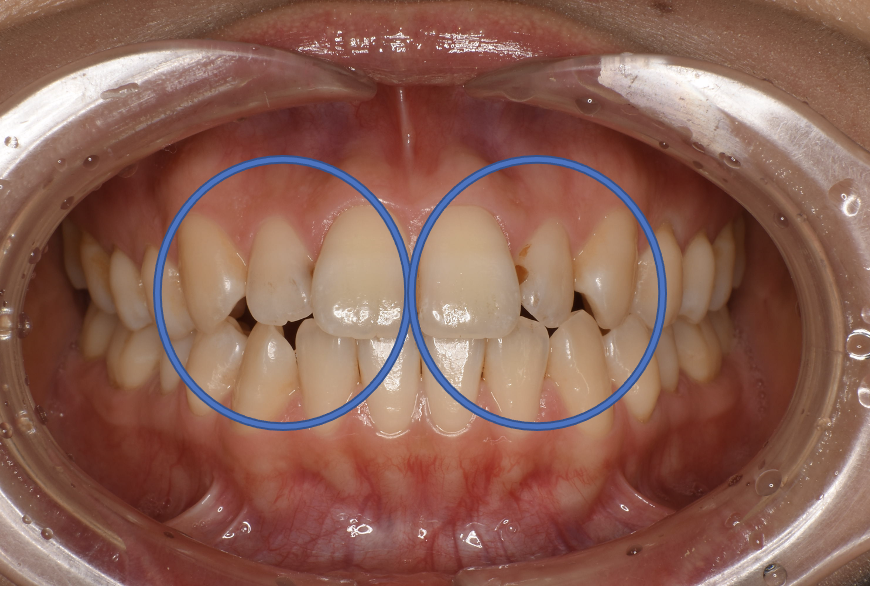

Before

| 治療方法 | ダイレクトボンディング ダイレクトボンディング治療は、セラミックによる被せ物(Cr)や詰め物(In)に比べて、歯を削る量を抑えることができます。天然歯は、明るく透明感のあるエナメル質、色が濃く透明性の低い象牙質、神経や血管がある不透明な赤色の歯髄の3種類の構造が重なり合って作られています。従来の歯科用プラスチック(コンポジットレジン)では、このような歯の複雑な質感を再現することが困難でした。近年、透明感や色調が豊富に揃った審美修復用プラスチックが開発され、多数の色調を積層築盛することで、天然歯のような自然な歯を再現できるようになりました。ハイブリッドレジンペーストで歯の形を作り、光で固めて強度を出し、磨いて艶を出し、自然な歯の形態を回復する方法です。 |

| 備考 | 院長より 前歯の虫歯に保険のプラスチックを詰める治療を以前に施されていました。しかし、残念ながら、二次的な虫歯になり、着色もしてしまい 見た目をとても気にされていました。天然歯のような自然観を回復することが出来、喜ばれています。 |